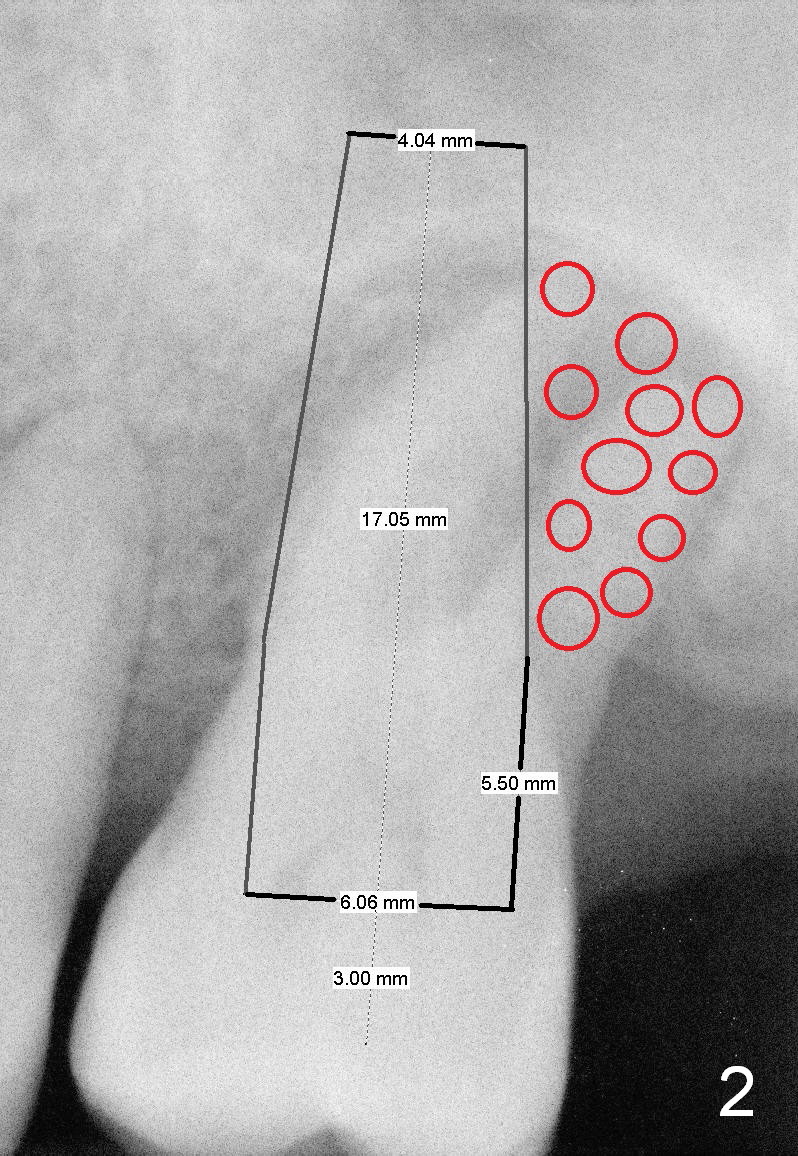

A 52-year-old man (DM) will return for #14 extraction and immediate implant nearly 2 years after #12 crown cementation. There is more bone loss distally than mesially. Clinically, the palatal recession is excessive (Fig.3). After socket debridement and 2% Xylocaine/1:50,000 Epinephrine gauze packing, osteotomy will be initiated in the buccomesial aspect of the septum, if the latter is present. Use 4.5 or 5x17 mm tap to test stability and more importantly determine how much thread exposure can occur palatally before placing a 14 or 17 mm long implant (Fig.2). A fair amount of bone graft will be inserted distopalatally (red circles in Fig.2). If primary stability is achieved, use an immediate provisional to close the socket opening.